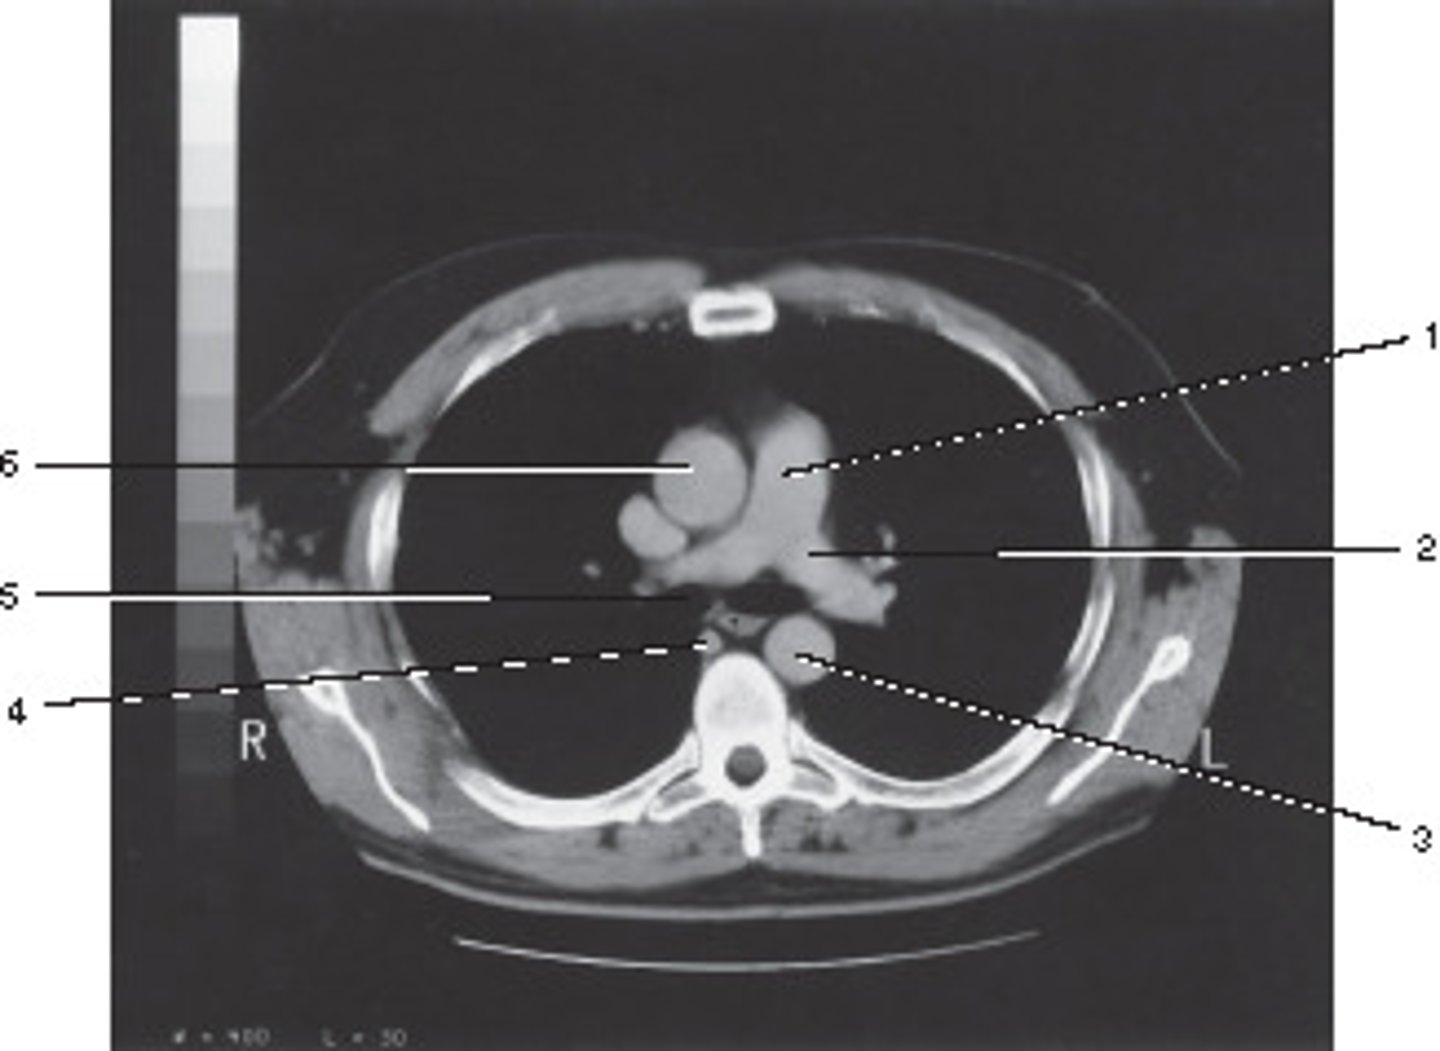

Number 2 corresponds to which of the following?

<p>Number 2 corresponds to which of the following?</p>

On the basis of the appearance of this image, what contast media was utilized?

<p>On the basis of the appearance of this image, what contast media was utilized?</p>

Descending Aorta

Number 1 corresponds to which of the following?

<p>Number 1 corresponds to which of the following?</p>

Azygous Vein

Number 4 corresponds to which of the following?

<p>Number 4 corresponds to which of the following?</p>

Right Brachiocephalic Vein

Number 6 corresponds to which of the following?

<p>Number 6 corresponds to which of the following?</p>

Which number corresponds with the right atrium?

<p>Which number corresponds with the right atrium?</p>